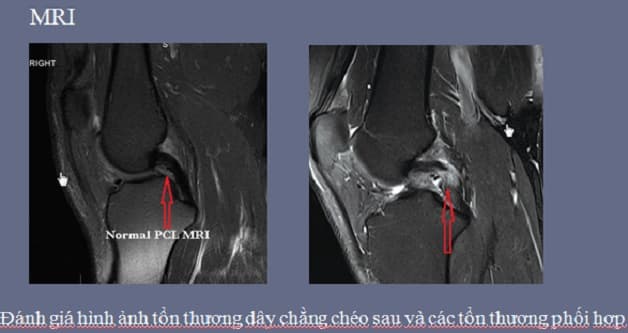

Chụp MRI khớp gối cũng như nhiều phương pháp chẩn đoán hỉnh ảnh khác, được sử dụng như một công cụ hỗ trợ các bác sĩ chẩn đoán tình trạng chấn thương, tình trạng bệnh lý ở khớp gối, tầm soát khớp gối. Trong các trường hợp đánh giá tổn thương sụn chêm, sụn khớp, dây chằng và xương thì chụp mri khớp gối đóng vai trò vô cùng quan trọng, giúp đưa ra kết quả chẩn đoán chính xác tình trạng tổn thương tại khớp gối.

– Đánh giá tổn thương sụn chêm, dây chằng, gân cơ và các tổ chức phần mềm vùng khớp gối.

Hình ảnh chụp mri khớp gối phản ảnh rõ nét các tổn thương dù nhỏ nhất, khó phát hiện mà bằng các phương pháp chẩn đoán hình ảnh khó có thể kết luận chính xác.